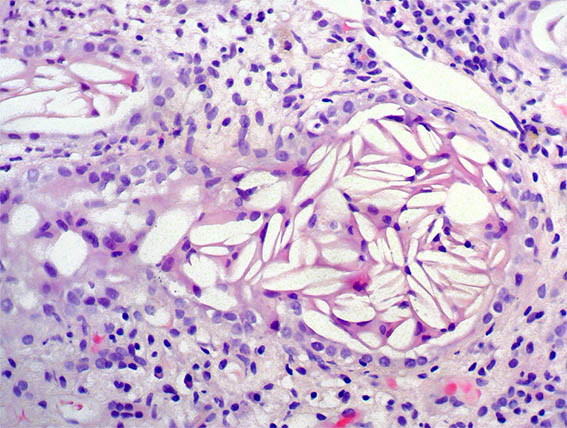

Figura 4. H&E, X100.

Figura 5. Tricrómico de Masson, X100. Observe lo que hay en algunos túbulos, los cuales están muy dilatados.